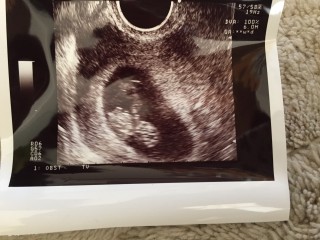

前回の健診から2週間後の姿です!可愛い姿が見れて嬉しかったです(^ω^)心拍もしっかりしてるし、また2週間後の健診が楽しみです。